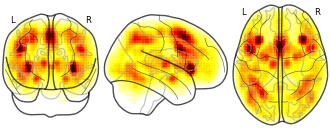

"name": "Multi_VBMgreater_fMRIenhanced",

"description": "Multi-modal analysis in BPD. Brain regions exhibiting greater gray matter and enhanced activation during emotion processing in BPD compared to healthy controls. Note: Results were thresholded at p<.0025. Note2: Results were updated (see Erratum for this publication).",